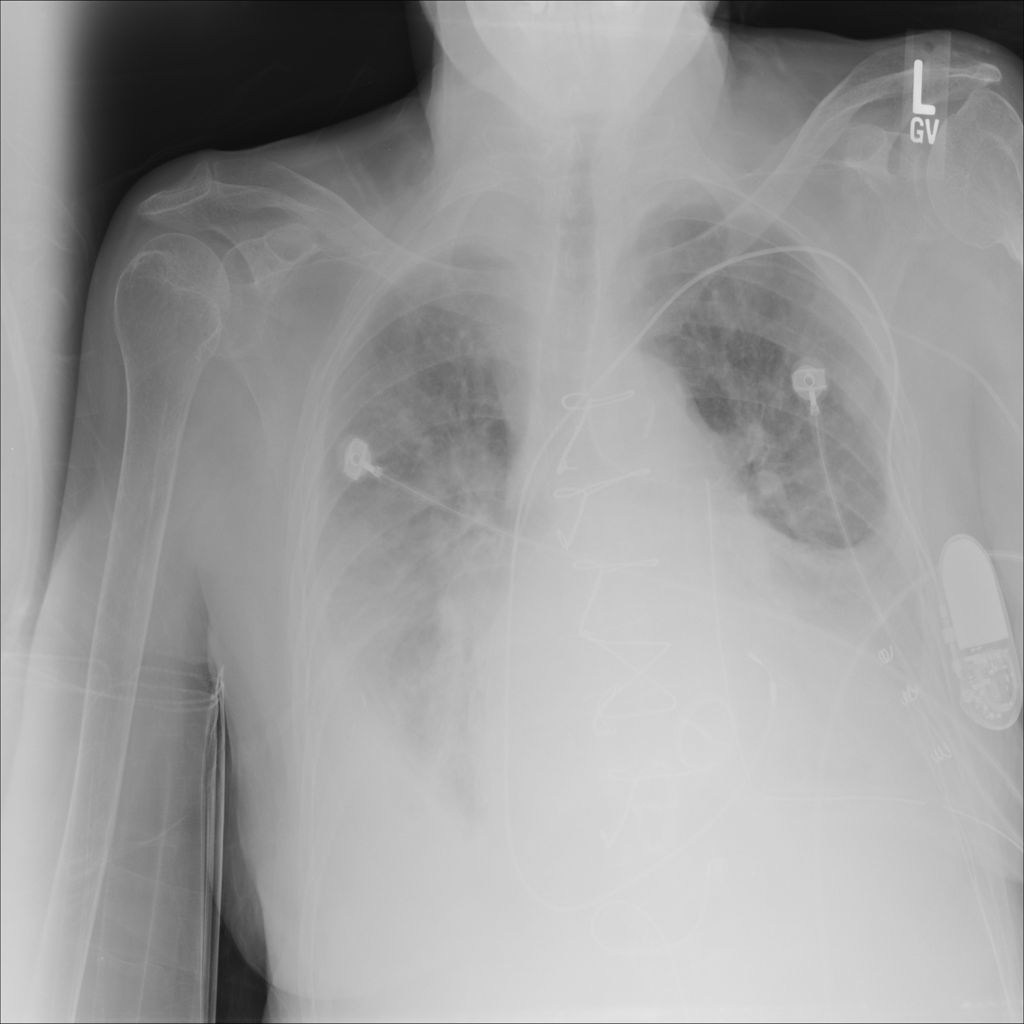

PAT-4639 · IMG-021Effusion

PAT-4639 · IMG-021

PA